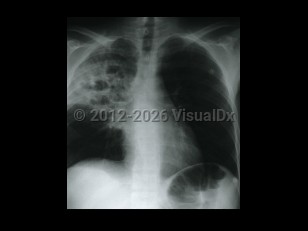

Chest pain, Pleural effusion, 50-59 year old Female

Pleural effusionPleural effusion

Hemothorax